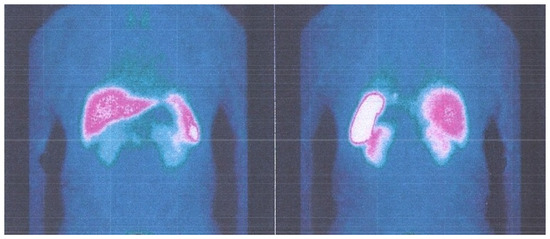

2. Case Report 1

3. Case Report 2

4. Case Report 3